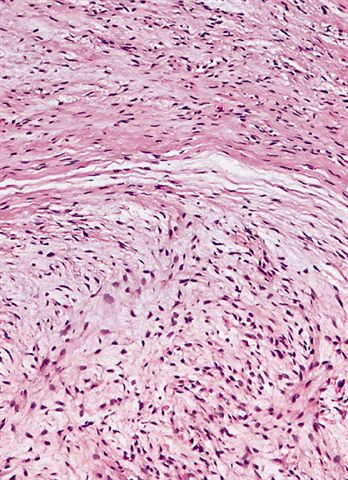

Microscopic (histologic) description

- Low to moderately cellular, bland fusiform or spindled cells with focal to diffuse whirling in heavily collagenized stroma with abrupt transition to myxoid areas

- 45% have epithelioid areas

- 40% contain poorly formed but large collagen rosettes

- Often infiltrates adjacent skeletal muscle

- Occasionally has areas of increased cellularity, atypia, necrosis or mitotic activity characteristic of intermediate to high grade sarcoma

- Recurrences may show increased cellularity and mitotic activity

Microscopic (histologic) images